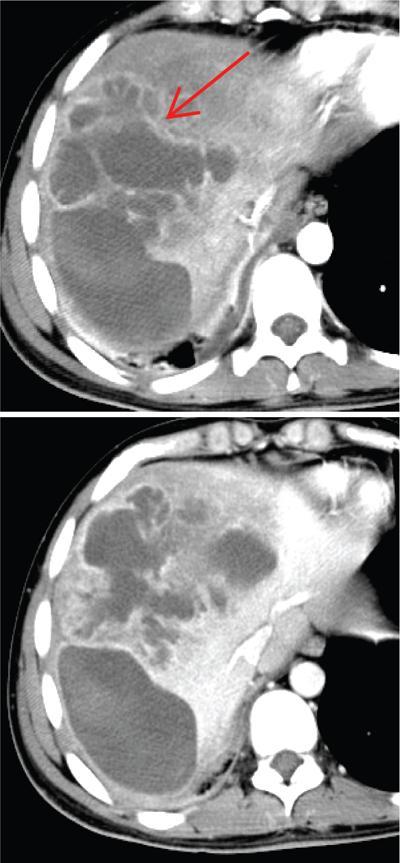

Shrinivas B. Desai, Ritu K. Kashikar, Shreya Shukla Radiological signs are classical and distinctive abnormalities characteristic of a disease. These can be seen on any imaging modality. Resemblance to commonly seen objects and patterns form the basis of radiological signs. The aim is to help the reader associate, understand and memorize these pathologies with the aid of signs. Various signs pertinent to hepatobiliary system are described in the chapter. Described on MRI when liver lesion shows a peripheral rim of high T2 signal intensity with the centre of the lesion appearing isointense to the background of noncirrhotic liver on T2WI mimicking an atoll. It is considered a characteristic sign of an inflammatory hepatic adenoma (image) but is only seen in about one-third of cases Extrinsic smooth impression over medial aspect of duodenum along its posteroinferior aspect, seen in pancreatic head pathologies like carcinoma. This sign is seen in pancreatic adenocarcinoma Presence of a persistently hyperattenuating dot within a lesion on arterial and portal venous CT. This corresponds with peripheral nodular enhancement seen on dynamic MR. Presence of bright dot suggests that the lesion is a hemangioma and helps in ruling out metastasis Ultrasound appearance of multiple cystic spaces or lesions that has been used to describe the appearance of an intraductal papillary mucinous neoplasm of the pancreas. Seen on contrast CT in portal hypertension. The appearance is based on resemblance to Medusa from Greek mythology. Dilated engorged paraumbilical veins radiating across umbilicus to join systemic veins is seen. This sign is seen in Caroli’s disease on contrast CT. Enhancing dots within dilated intrahepatic bile ducts represent portal radicles. Caroli’s disease Irregularly dilated pancreatic duct with multiple strictures and intervening dilatation with associated dilated side ductules resemble multiple lakes supplied by a single territory. Best seen in MRCP images. Chronic pancreatitis It is a finding on MRI and CT and is best seen on MRI T2-weighted and postcontrast T1-weighted sequences. Small necrotic/purulent areas in the pyogenic abscess ‘cluster’ together and then coalesce into a larger necrotic/purulent areas, eventually becoming a larger septated abscess cavity. At the periphery of these clusters: Associated with pyogenic hepatic abscesses and can help differentiate pyogenic abscesses from other types of liver lesions Abrupt termination of gas within the proximal colon at the level of radiological splenic flexure. The inflammatory exudates in pancreatitis extend to the phrenicocolic ligament giving rise to this sign Seen on grey scale ultrasound as a reverberation artifact when small calcific or highly reflective objects are imaged. The colour comet-tail artifact is an ultrasonographic sign seen in a number of situations when colour Doppler scanning is performed. This sign occurs in cases of traumatic right-sided diaphragmatic rupture with resultant partial herniation of liver through the defect. Separation of the herniated liver from its intra-abdominal component is via a small constriction at the level of diaphragm resembling a cottage loaf. Cottage loaf is a particular shape of bread in which larger and smaller roughly spherical balls are squashed together. Traumatic right-sided diaphragmatic rupture with resultant partial herniation of liver Bile eccentrically outlines luminal stone, creating a low attenuation crescent. Best seen on MRCP images. Choledocholithiasis Dilatation of both pancreatic duct and CBD is referred to as the double duct sign. Positive double duct sign suggests the diagnosis of carcinoma of the head of the pancreas and ampullary tumours and is hence considered ominous. Occasionally the sign may be seen in impacted gallstone in the distal duct. This feature is seen in patients with liver abscess on contrast-enhanced CT. A double, inner hyperattenuating and outer hypoattenuating rim is seen surrounding the hypodense abscess. The inner hyperattenuating rim corresponds to the enhancing abscess membrane, while the outer rim corresponds to the edema of the surrounding liver which appears hypodense and may show delayed enhancement. Liver abscess A positive duct penetrating sign is when a mass is penetrated by an unobstructed pancreatic duct; this makes focal pancreatitis the most likely cause rather than pancreatic carcinoma. This sign is best appreciated on MRCP (or ERCP). A radiographic sign that can be useful in differentiating between focal pancreatitis (inflammatory pancreatic mass) from pancreatic carcinoma. The duct-penetrating sign on MRCP is more helpful in differentiating between these two entities than a delayed enhancement pattern on CT or MRI It occurs when there is both limy bile and a gallstone in the common bile duct. The linear vertical radiopaque bile forms the line of the exclamation mark (i.e. !), whilst a more distal calculus forms the ‘dot’ at the end of the exclamation mark. Pathognomonic imaging sign of the rare diagnosis of limy bile on plain abdominal radiography Nonenhancing ruptured lesion with peripheral rim enhancement showing discontinuity from the rest of the liver and protruding from the liver surface is called the enucleation sign. Ruptured HCC Enlargement of the pericholecystic space. One of the signs of liver cirrhosis Can be seen on technetium 99m sulphur colloid scans of the liver and spleen, as well as CT studies. It occurs as a focal area of increased radiopharmaceutical uptake in the medial segment of the left hepatic lobe (segment IV) occurring as a result of SVC obstruction and portosystemic venous shunting between the superior vena cava and the left portal vein via the internal thoracic and paraumbilical veins. The equivalent of this sign may also be seen on contrast-enhanced CT scans as a hypervascular region. Budd–Chiari syndrome causes the hot spot sign in the caudate lobe